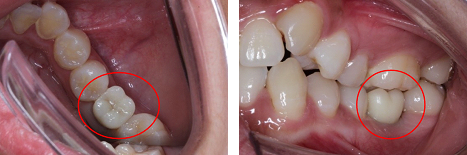

戴牙后照片

本次手术由于采用了微创种植技术,所以手术过程中出血非常少,对患者牙龈和牙槽骨组织起到最大的保护作用,术后患者只需用冰袋冷敷,预防肿胀,并不需要服用抗炎药物。医生表示手术很成功,约三个月后植体上部牙冠戴入,即缺牙区二期修复,同时两侧好牙未遭到任何损坏。